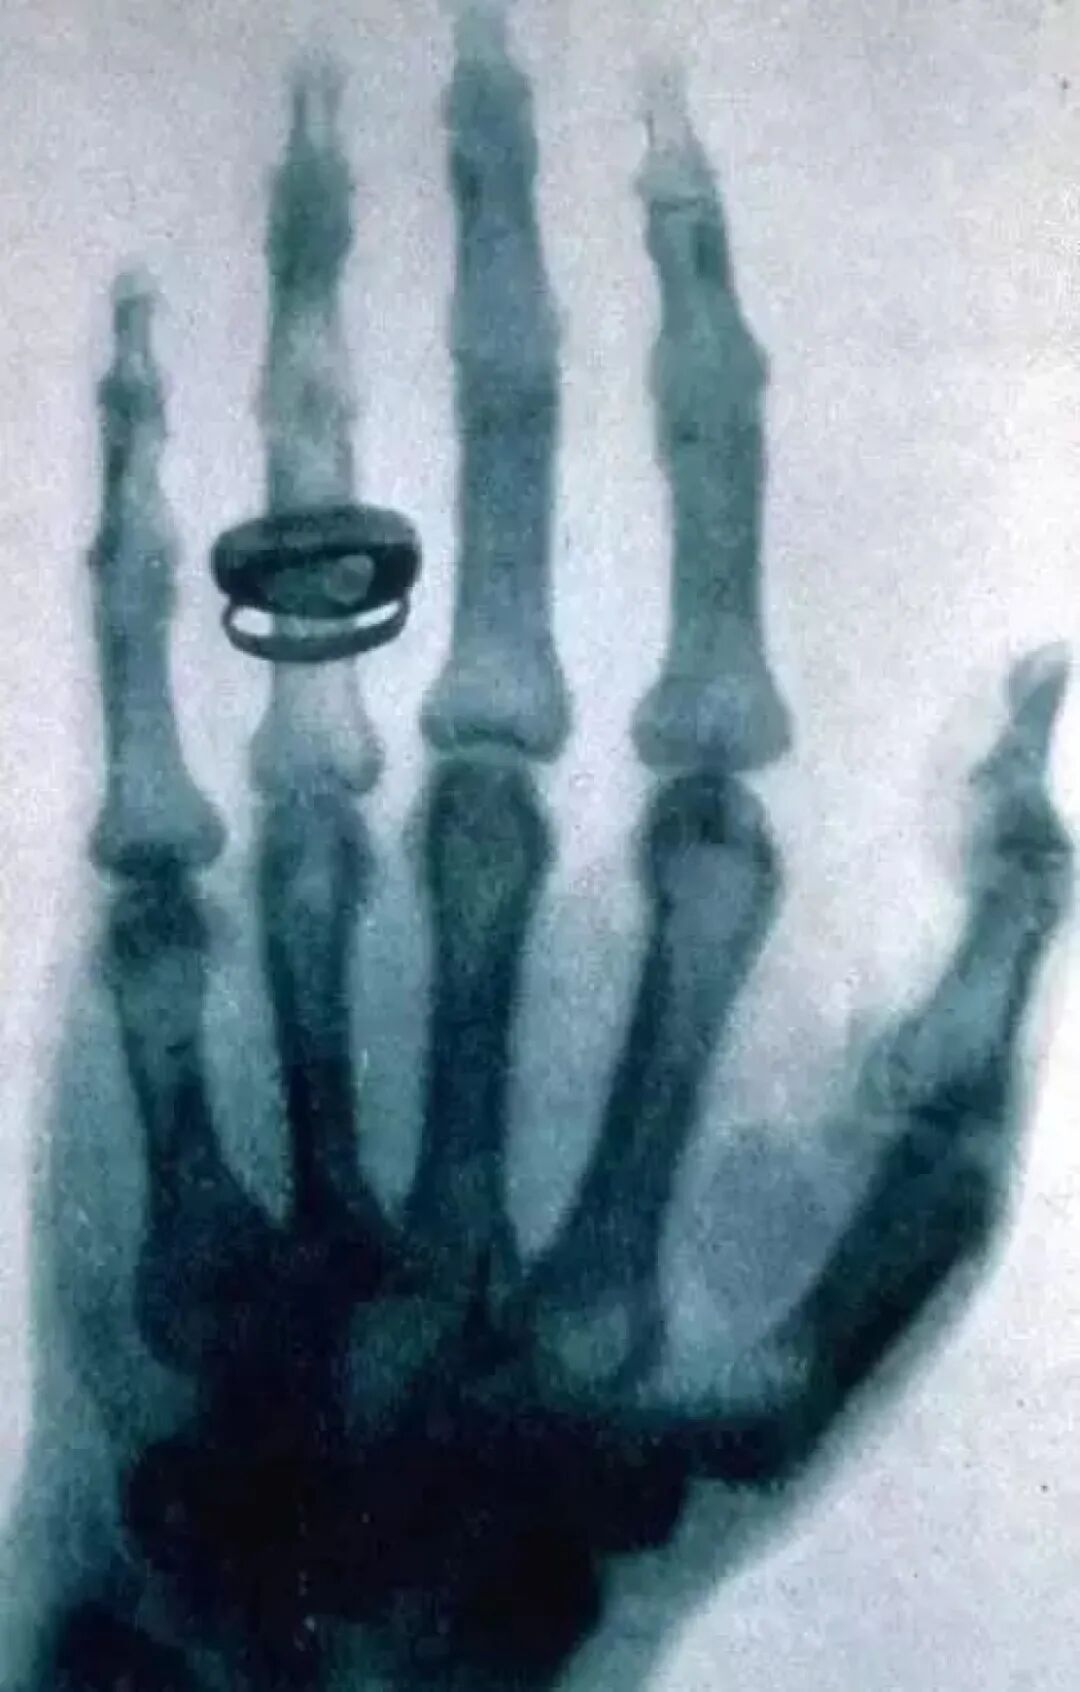

当他觉得这种新发现的光已经确信无疑,已经过去了7个星期了。1895年12月22日晚上,他说服了自己的夫人来当实验对象,当他夫人将自己带有戒指地伸向荧光屏时,令人震惊而奇异的现象出现了,伦琴夫人看到一只瘦骨嶙峋的手,再仔细一看,那不是手,而是一个个骨节。

夫人不敢相信,这就是自己的手?但在影子的无名指骨节上,分明有一个戒指,与自己戒指戴的位置一点都没有偏差!伦琴夫人被自己的手吓住了,要知道那个年代还有谁看到过这种影像?只有死人的白骨才会这样。

而这是人类第一张X光照得的人体照片!伦琴异常激动地拥抱了夫人。终于证实了,这是一种前所未有的光,能够穿透肉体的光。